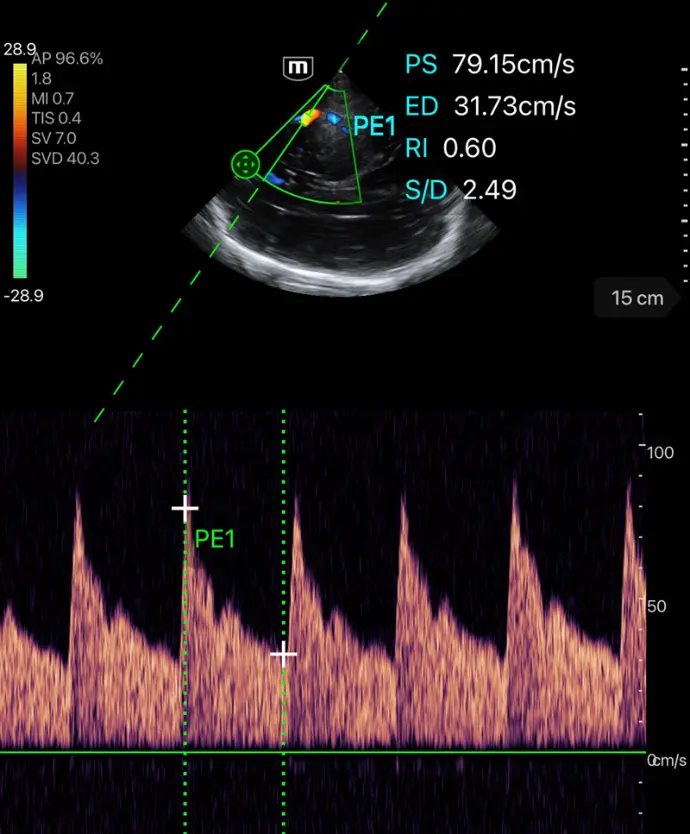

PW Auto Trace - автоматично PW трасиране и калкулации на PS, ED, TAMAX, TAMEAN, RI, PI, S/D, HR

PW Auto Calc

Aвтоматично PW трасиране и калкулации на PS, ED, TAMAX, TAMEAN, RI, PI, S/D, HR

Клинични снимки